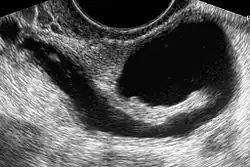

The examination can be performed by transabdominal ultrasonography, generally with a full bladder which acts as an acoustic window to achieve better visualization of pelvis organs, or by transvaginal ultrasonography with a specifically designed vaginal transducer. Transvaginal imaging utilizes a higher frequency imaging, which gives better resolution of the ovaries, uterus and endometrium (the fallopian tubes are generally not seen unless distended), but is limited to depth of image penetration, whereas larger lesions reaching into the abdomen are better seen transabdominally. Having a full bladder for the transabdominal portion of the exam is helpful because sound travels through fluid with less attenuation to better visualize the uterus and ovaries which lies posteriorly to the bladder. The procedure is by definition invasive when performed transvaginally. Scans are performed by health care professionals called sonographers, or gynecologists trained in ultrasound.